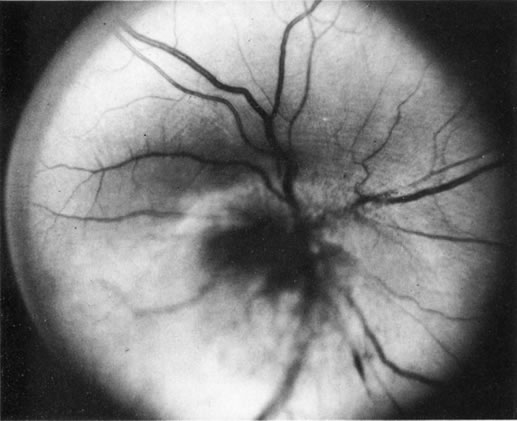

Unfortunately, imaging studies are not always diagnostic. The A- and B-scans shown in Figures 3 and 4 were from a patient with unilateral media opacity referred for evaluation and treatment of a presumed uveal melanoma. Occasionally, if the cataractous lens is scanned tangentially, artifact can occur. A repeat ultrasound at our institution was negative for tumor, and the referral ophthalmologist who performed a cataract extraction noted that no tumor was present and that the patient has an excellent visual outcome. In contrast, the patient shown in Figure 5 was referred with a presumed uveal melanoma with secondary inflammation and a history similar to that described for the patient shown in Figure 111 Ultrasound and CT examinations were not diagnostic. Because the eye was blind and painful, it was enucleated, and an extremely necrotic uveal melanoma was noted histologically. In some necrotic melanomas, the fundus cannot be visualized and the diagnosis cannot be established with imaging studies. Very rarely, a necrotic uveal melanoma can produce sufficient pigment dispersion into the vitreous to obscure the correct diagnosis.12

Fig. 5. Clinical appearance of an eye with inflammation and pain. Ultrasound and CT were not diagnostic. Histologic examination revealed a necrotic melanoma.